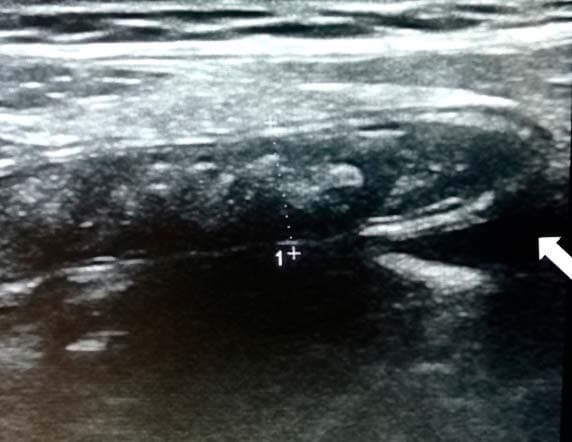

Аппендикс считается расширенным, если под действием компрессии его наружный переднезадний размер, измеренный при поперечном сканировании, более 6 мм (см. рис. 3).

Рисунок 3. Определение диаметра аппендикса.